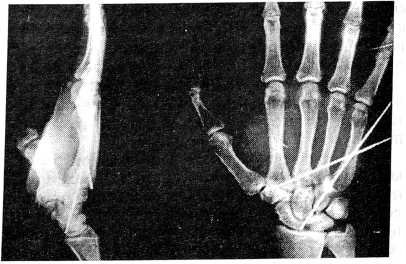

Рис. 2.

Рис. 3.

Г., 29 лет, обратился в приемное отделение НИЦТ “ВТО” 24.11.96 г. после падения на лестнице и сильного удара с упором на локтевой край правой кистью. При клинико-рентгенологическом обследовании установлен редкий случай изолированного вывиха четырех пястных костей (рис. 1). Под местной анестезией 2% раствором новокаина вывих был вправлен, и наложена ладонная гипсовая лонгета (без разгибания кисти и упора на область головок пястных костей!). На контрольных рентгенограммах после вправления выявлен подвывих 2—3—4—5-й пястных костей (рис. 2). Однако больной от повторного вправления подвывиха и госпитализации отказался. Через неделю из-за усилившихся болей в области кисти лонгета была снята, и рентгенограммы показали полный (повторный!) вывих 2—3—4—5-й пястных костей (рис. 3). Под внутривенной анестезией 2% раствором новокаина вывих пястных костей был вправлен и произведена чрескожная чрескостная фиксация двумя спицами сроком на 6 недель (рис. 4). Осмотрен через год, функция правой кисти полная, жалоб не предъявляет.

Рис. 4.